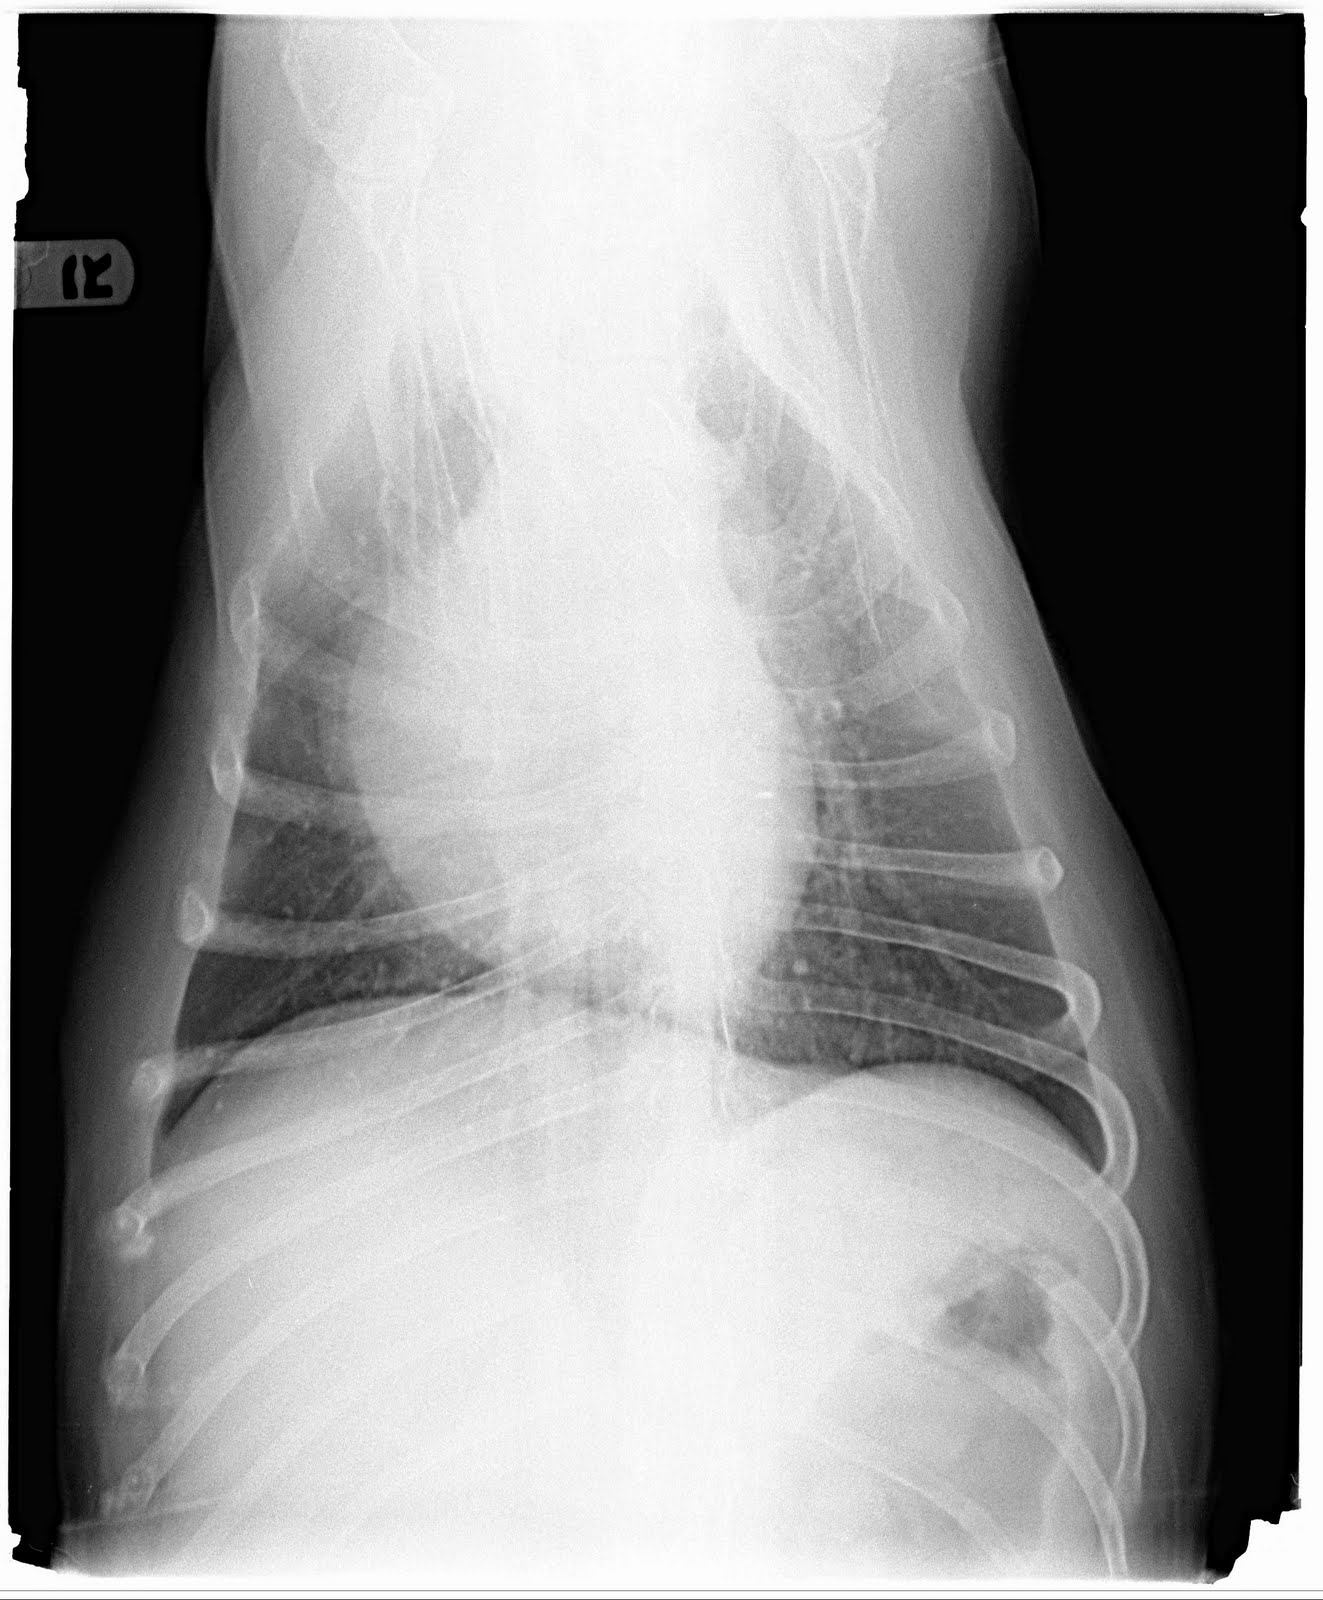

Compressed Lungs In Dogs . This means that anything that fills some of the space where the lungs should be could potentially cause your dog to breathe faster than normal or have trouble breathing. Fortunately, respiratory distress—no matter what the cause—requires somewhat standardized interventions during initial stabilization. Damage to the chest wall or lung caused by injury. pneumothorax can occur in three different ways. some common breathing conditions in dogs are: It happens when air builds. The lungs must have room to expand in the chest in order for the dog to breathe properly. managing dogs and cats in respiratory distress is a multifaceted effort that involves stabilizing patients prior to determining a definitive diagnosis. pneumothorax, often known as a collapsed lung, is a potentially fatal illness that can occur in dogs. ventrodorsal thoracic radiograph of a dog with bronchopneumonia involving the right middle lung lobe.